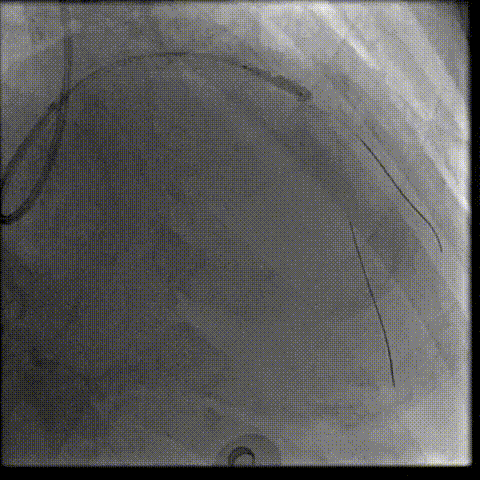

LAD近段-LM IVUS提示为270°环形钙化

LAD近段-LM 选择shockwave4.0*12mm,间断触发脉冲,每5个脉冲为一组,只4atm治疗,防止患者缺血省略6atm扩张,每次回撤Guiding,使用5个周期;

复查LAD近段-LM IVUS,钙化环明显断裂

于LAD-LM开口分别植入3.5、4.0两枚支架